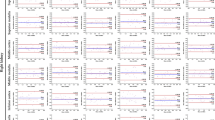

Controlled-breathing dynamic DWI scans were performed to determine if breathing motion can cause intravoxel dephasing. Supplementary Material Fig. S1 shows example images from a single subject, and Fig. 1 shows the single-shot and multi-shot controlled breathing (deep vs. shallow) results for one subject. In the single-shot case, the DWI signal CV without pF was larger with deep breathing than with shallow breathing, most likely because of increased signal loss due to motion during the diffusion encoding of individual measurements, which lead to a larger signal variation over all measurements. As the pF factor was reduced, the signal CV increased. In the deep-breathing single-shot case, there were much larger differences in signal CV between subsequent pF factors as the pF factor was reduced below 0.65, and there were many data points where there was a large drop in signal when using low pF factors in comparison to no pF, suggesting that breathing motion can cause intravoxel dephasing which can be exacerbated using lower pF factors in prostate DWI. Supplementary Material Fig. S1 shows many cases of severe signal loss in the single-shot deep breathing case. In the multi-shot case, the signal CV was low for both deep and shallow breathing in comparison to the single-shot case. However, as the reconstructed images are from 2 shots, there is an averaging effect in the signal intensity from combining the shots, which will then have an averaging effect in the signal CV. Figure 2 shows the signal CV over all subjects. In general, the signal CV is higher for deep breathing in comparison to shallow breathing, in both single-shot and multi-shot cases. Lower pF values also in general have higher signal CV values than higher pF values.

Signal intensity and CV of signal intensity over an ROI over all repetitions for a range of simulated partial Fourier factors in a single volunteer. Both deep and shallow breathing acquisitions were performed, for both single-shot and multi-shot (2 shots). The multi-shot acquisition was 2 shots for 20 repetitions and, therefore, had the same number of total acquisitions as the 40 repetition single-shot acquisition. In the single-shot deep breathing case, there is a clear increase in signal variation as the partial Fourier factor is decreased, whereas in the single-shot shallow breathing case, the signal variations are much smaller compared to the deep breathing case. There are also some data points where using a low pF causes a large signal drop compared to no pF, which may be due to motion. The signal variation in the deep breathing multi-shot case is smaller than the single-shot deep breathing case, which may be due to the fact each repetition is the combination of 2 separate acquisitions, which has an averaging effect. There is not much signal variation in the multi-shot shallow breathing case

CV of signal intensity over all subjects, with the deep breathing results shown in blue and shallow breathing results shown in red. In both single-shot and multi-shot cases, deep breathing has a higher CV than shallow breathing. The simulated pF factor of 0.55 also has the highest signal CV in all cases. The multi-shot cases in general have lower signal CVs than the equivalent single-shot cases, probably due to the averaging effect of acquiring multiple shots